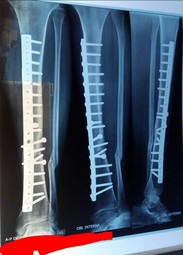

From La Patita incident, xray's took 20 days ago, everything is fine according with the Doc, he says that bone will fix alone but it will take 5-6 months more, and some pics from the clĂ­nica, they have some other nice fĂștbol articles.